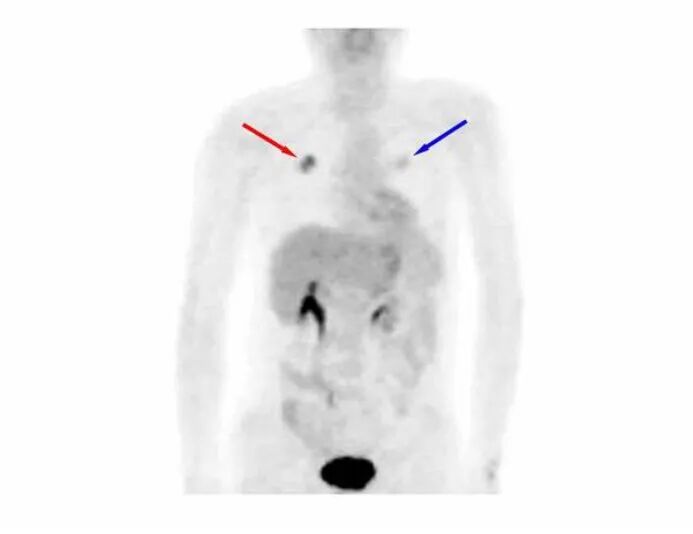

一眼看懂PET-CT原理作者: 田耕医生 肿瘤科主任医师 PET-CT的全称叫正电子发射断层显像-X线电脑体层成像,实际上是由PET和CT两种设备组合而成,即一个过程同时做了PET和CT两种检查。同时提供解剖显像和功能显像,是目前影像诊断技术中最为理想的结合。特别是在肿瘤的诊断、分期、疗效评估等方面发挥重要的作用。CT检查已被广泛应用,其原理大家已经有所了解。那么PET-CT的原理是什么?PET-CT的原理包括两部分:1.PET的显像原理;2.PET与CT的图像融合。下面我们先来看PET的显像原理。 为了更好的说明这个问题,从下面这个例子入手可能更好理解:现在有两颗黄豆,一颗是炒熟的,但颜色没变,另一颗没炒,你有什么方法把它们鉴别开吗? 图一:你能说出哪一个是炒熟的黄豆吗? 显然,从颜色、形状、大小、质地、轻重等方面无法将它们区分开,但它们是有本质区别的:炒过的黄豆是没有活性的,而没炒的黄豆是有生物活性的,当给予适当的温度和水,它会长成豆芽。因此它们的区别在于是否有活性: 图二:炒过的黄豆是没有活性的,是“死”的,而没炒的黄豆是有生物活性的。 如果有一种方法能够鉴别是否有活性,就能够将它们区别开。 PET就是这样一种检查,可以检查出不同病灶的代谢活性,从而为鉴别诊断提供重要资讯。恶性肿瘤有一个共同的特性就是代谢活性非常高。它是人体内的「强盗」,掠夺性的摄取营养,往往是肿瘤患者越来越瘦,可肿瘤却越长越大。葡萄糖是人体细胞(包括肿瘤细胞)能量的主要来源之一,因此恶性肿瘤摄取的葡萄糖远远多于其它正常组织。利用这一特性,在葡萄糖上标记上带有放射活性的元素氟-18作为显像剂18F-FDG,将此显像剂注入静脉内,在体内回圈,恶性肿瘤摄取的18F-FDG远多于其它组织,因此,肿瘤细胞内可积聚大量18F-FDG,经PET显像可以检测到体内18F分布情况从而显示肿瘤的部位、形态、大小、数量及肿瘤内的放射性分布。 我们来看一个临床应用的例子:一位患者因咳嗽咳痰就诊,痰中查见癌细胞,医生给他做了胸部CT,结果如图三: 图三:哪个病灶是癌?两个病灶都是癌? CT看到这位患者左右肺各有一个占位元病灶,增强扫描也未能提供足够的信息来判断出每个病灶的性质。于是这个患者的诊断有下列几种可能:1.右肺癌,左肺良性占位病变,如无远处转移,可能需要行右肺手术;2.左肺癌,右肺良性占位元病变,可能需要行左肺手术;3.双肺均为癌,则要双肺同时治疗。可见弄清楚诊断是多么重要,错误的诊断意味着错误的治疗。纤维支气管镜和肺穿刺活检是临床常用的方法,但如果能有一种无创、简便的方法将两个病灶鉴别开来该多好。 这位患者做了PET检查,结果如图四: 图四:左侧病灶(红色箭头,右肺病灶)是高代谢病灶,考虑为癌。 可以看到图中左侧的病灶(红色箭头,右肺病灶)呈现较深的黑色,表示摄取了较多的18F-FDG,是一个高代谢病灶,考虑为恶性肿瘤;右侧的病灶(蓝色箭头,左肺病灶)颜色很淡,表示摄取18F-FDG不多,是一个低代谢病灶,考虑为良性病变。患者痰中已查到癌细胞,因此,该患者的诊断已经明确:右肺癌,身体其它部位未见转移。最后接受了右肺手术治疗。 上一篇肾移植术后患者需知下一篇从微生物角度看医学实践 |